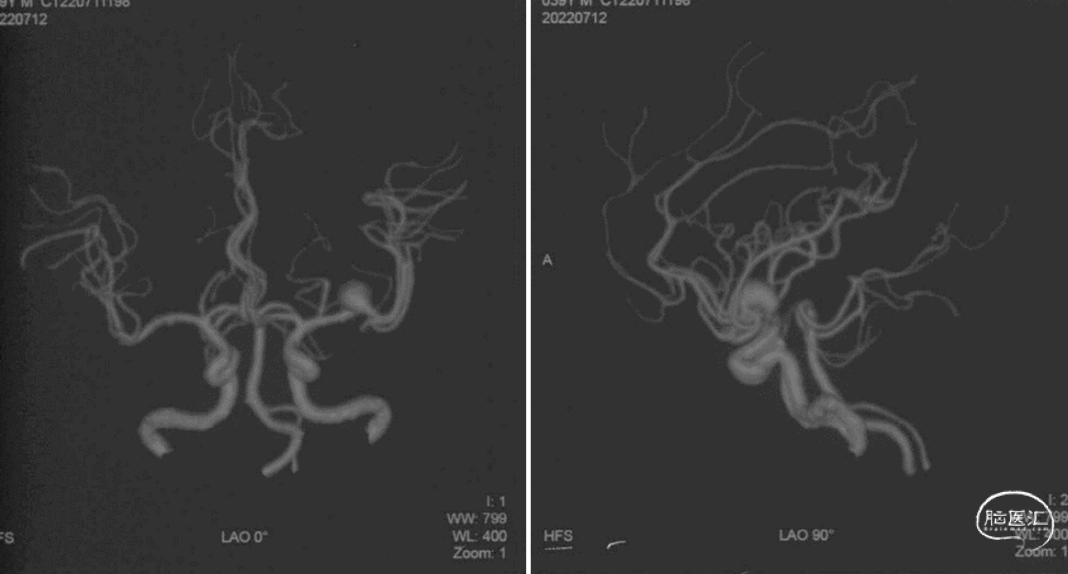

术前头颅MRA示:L-MCA分叉处夹层动脉瘤(07-12)。

正位

斜位

DSA检查:L-M1段夹层动脉瘤(07-28)。

1. 患者L-M1段夹层动脉瘤,约14.0*7.2mm,远端M2段血管管径约3.52mm,近端M1段血管管径约3.6mm。